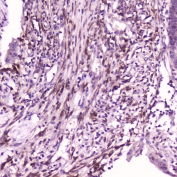

IHC testing of FFPE human intestinal cancer with IL36A antibody at 2ug/ml. HIER: boil tissue sections in pH6, 10mM citrate buffer, for 10-20 min followed by cooling at RT for 20 min.